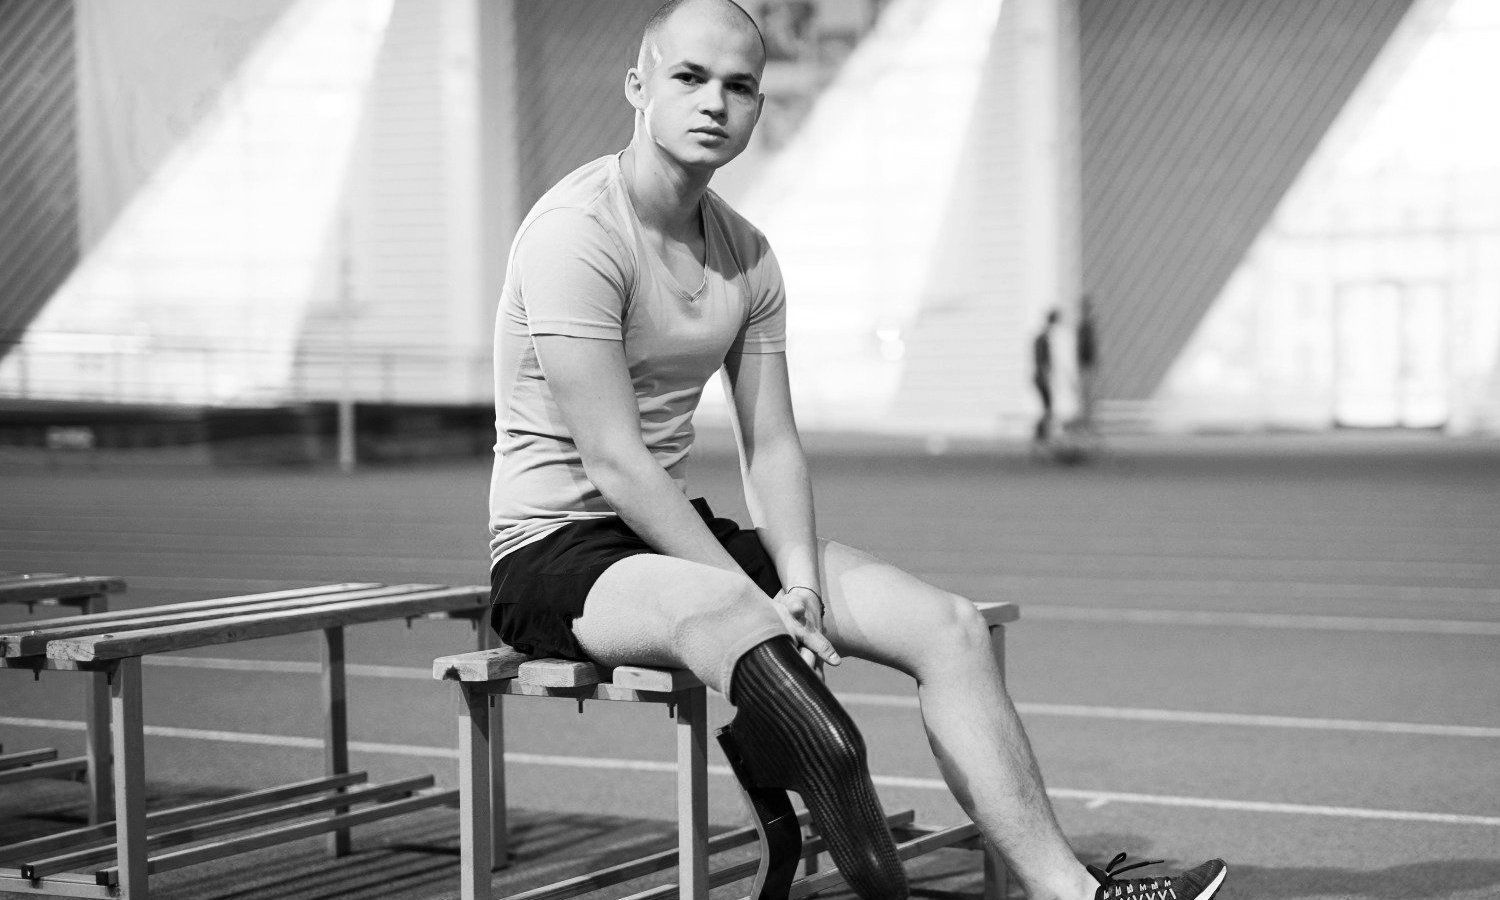

Targeted Muscle Reinnervation (TMR)

A modern surgical technique for treating transected nerve endings.

By Sunishka Wimalawansa, MD & Ian Valerio, MD